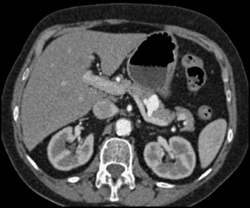

Diagnosis

Aortic Valve Replacement